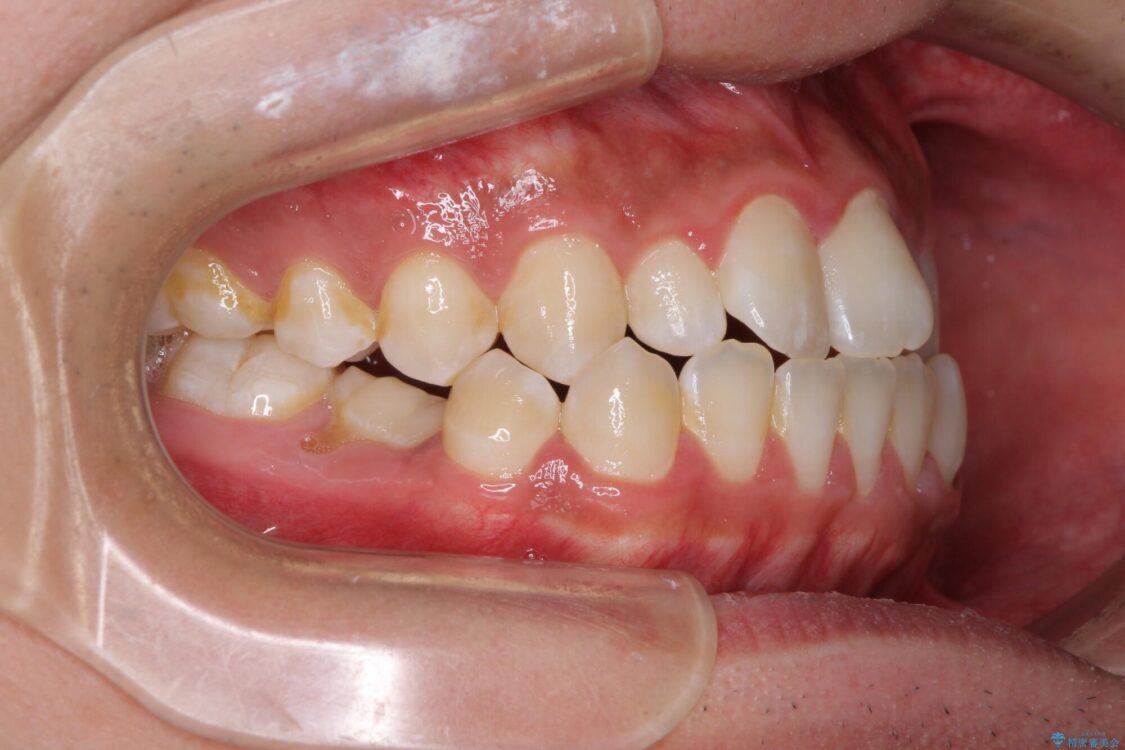

受け口傾向特有の狭い上顎歯列であったため、歯列の拡大を補助装置で行い、下顎歯列全体を後方に移動させることとしました。

奥歯の咬み合わせを改善させた後、上下左右の小臼歯(下顎は残存乳歯)を計4本抜歯し、ワイヤー装置にて口元の突出感を改善しながら咬み合わせを整えることとしました。

治療後について

下顎の残存乳歯は小臼歯よりも大きいため、スペースを閉じるために長い期間を必要としますが、予想通りに長期間を要することとなりました。

受け口傾向の方の抜歯矯正は、下顎前歯が舌側に倒れることで歯肉退縮を起こしやすいことが知られていますが、ワイヤーに工夫をすることでリスクを軽減させています。

治療後

• 口元の突出感を改善 受け口傾向の咬み合わせの抜歯矯正 治療後画像